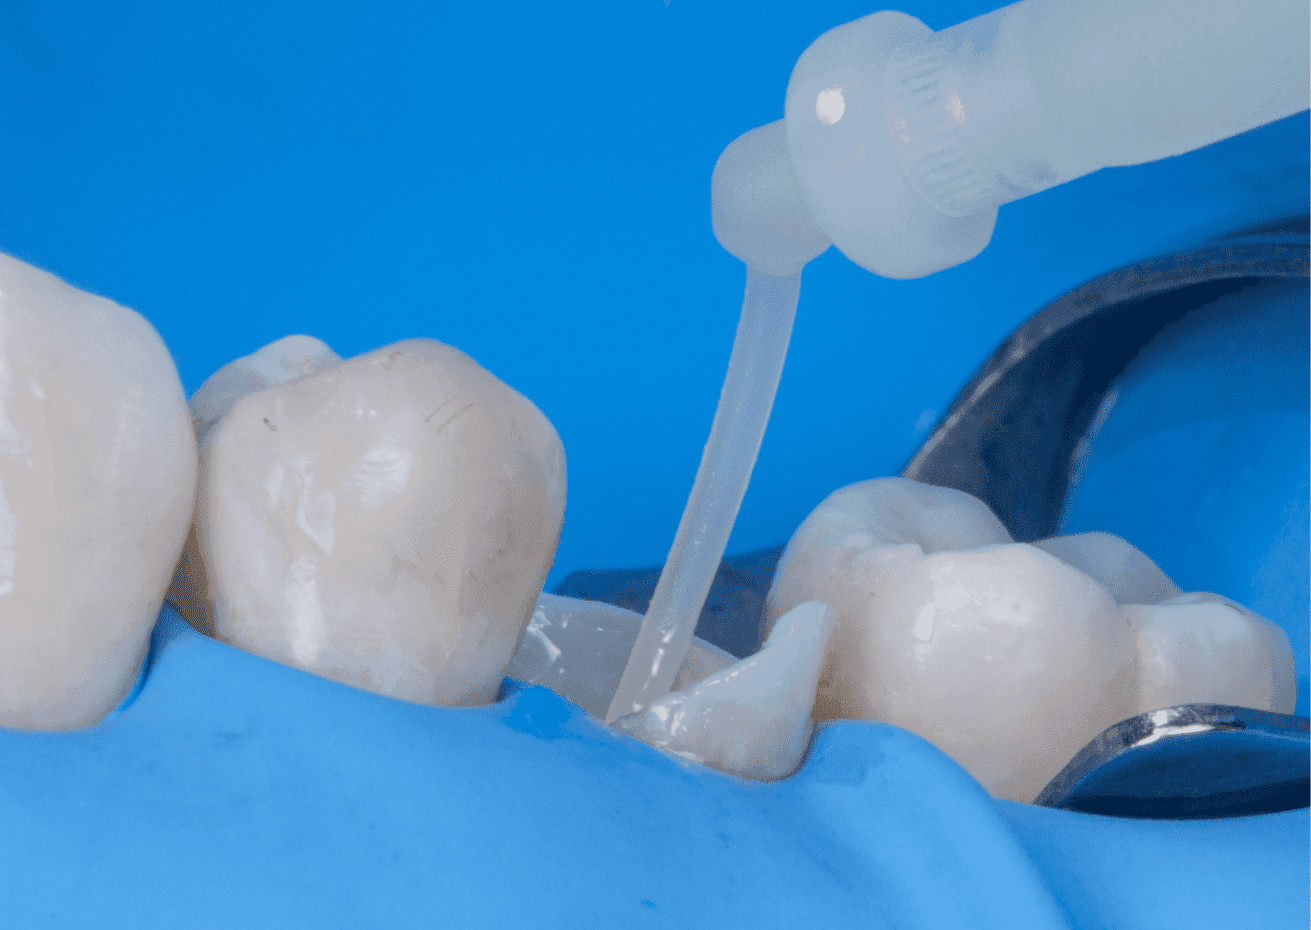

No planejamento reabilitador, foi reabilitado com dois pinos Whitepost SYSTEM cimentados com a combinação de sistema adesivo Ambar Universal APS e cimento resinoso dual Allcem CORE, que também foi utilizado para construção do núcleo de preenchimento.

A restauração final foi realizada utilizando scanner digital e coroa em resina vitrocerâmica BRAVA Block usinada em CAD-CAM, também foi cimentada com cimento resinoso dual Allcem CORE.